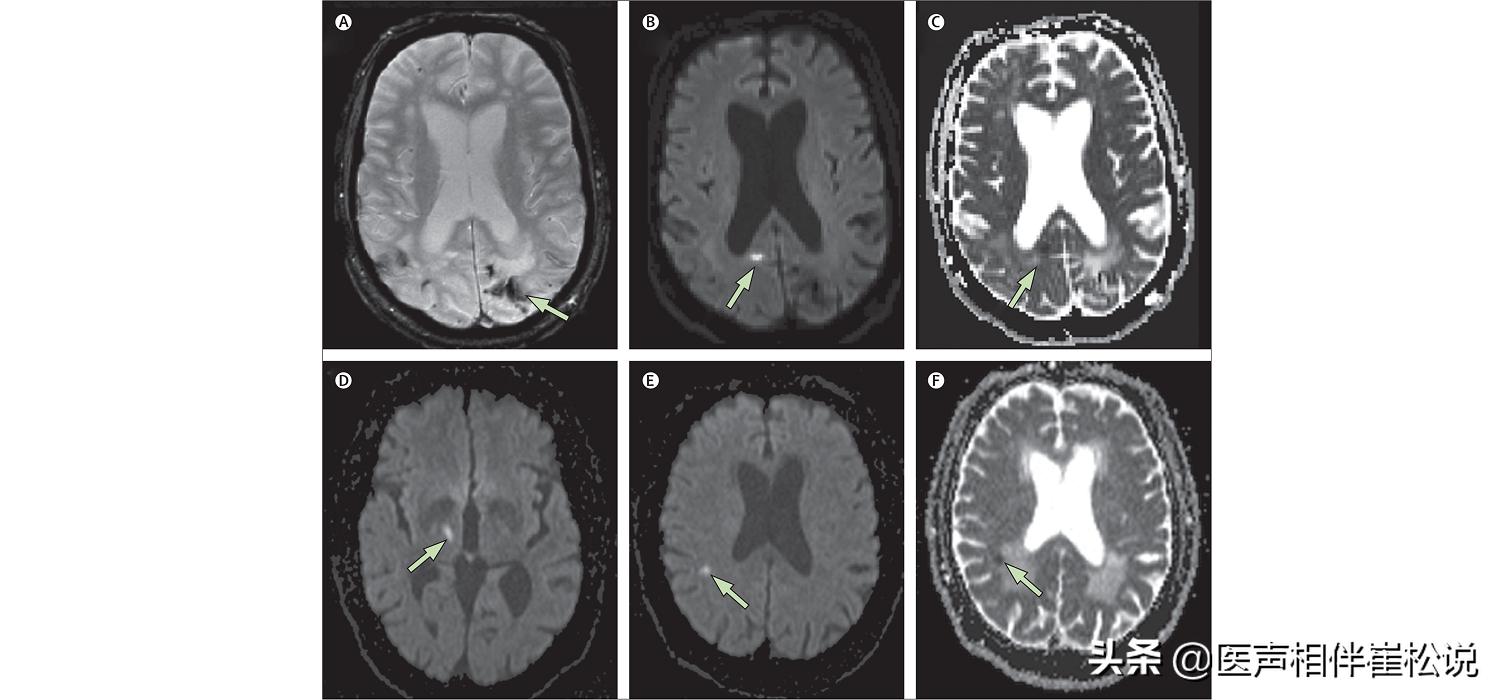

脑梗≠腔梗

有些人看到头颅CT报告上面写“基底节区多发性腔隙灶”,会问:“为什么我没有任何症状?我是不是要脑梗了呀。”但我要告诉你们的是,其实腔梗不等于脑梗。

脑梗一般是比较大的动脉堵塞引起的脑部一大片缺血而引起的功能障碍,是脑动脉硬化导致血管逐渐狭窄被血栓堵住而形成的一种疾病。

腔梗仅仅是小动脉硬化以后造成的局部小问题, 是没有血栓的。

脑血管本来只有2-4mm粗,脑动脉硬化以后血管管腔逐渐增厚,导致血流不能通过,这个过程是慢性的,它周围的组织出现营养不良就会慢慢软化,形成一点点小的软化灶,就叫腔隙性软化灶,所以动脉粥样是存在的,但并没有血栓,四分之三以上的腔梗是没有任何症状的,只有在做头颅CT的时候才能发现。